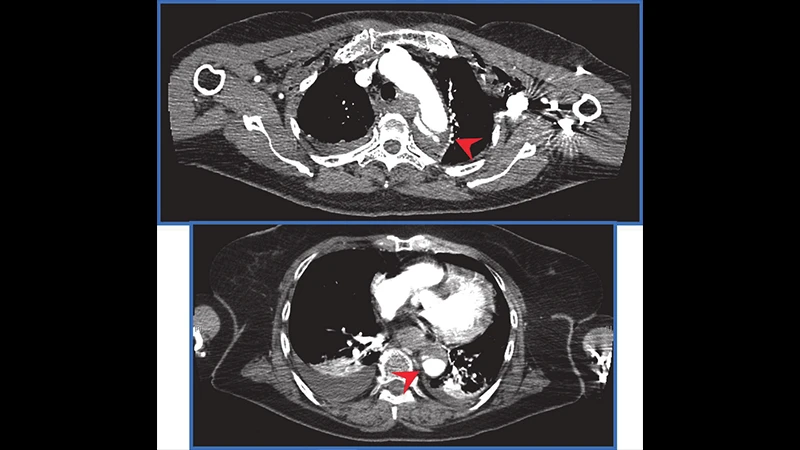

- Chest CT: Provides a much more detailed view than an X-ray, able to detect subtle lung contusions, small pneumothoraces, and injuries to the aorta and other major vessels.

- Abdomen/Pelvis CT: The most important part for identifying internal injuries. It can show lacerations to solid organs like the liver, spleen, and kidneys, as well as signs of active bleeding ("contrast extravasation").